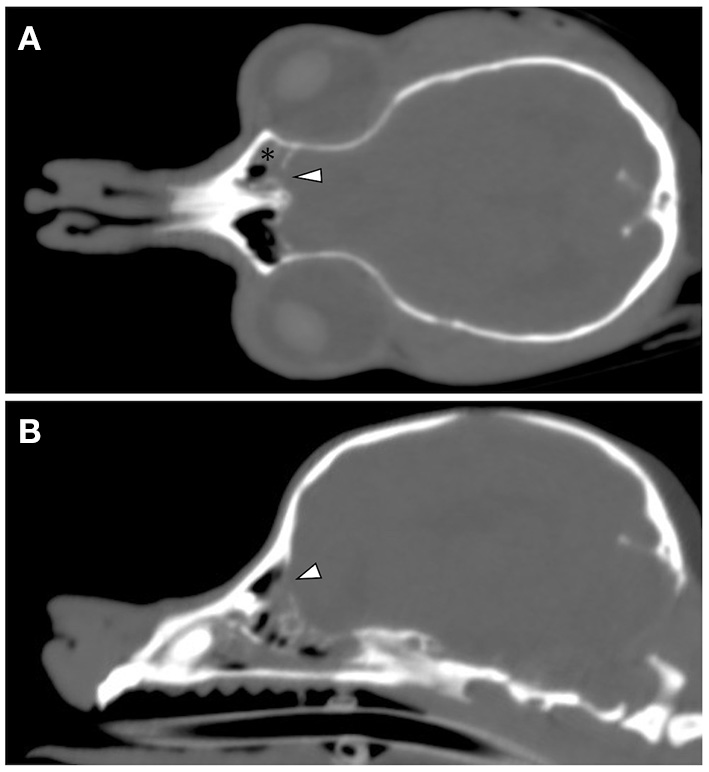

CT and MRI were undertaken to examine the cerebrum and diencephalon. Anesthesia was induced by propofol (MSD Animal Health, Tokyo, Japan) at a dose of 5.0 mg/kg and was maintained by isoflurane (MSD Animal Health). MRI was performed using a 0.4 T unit (APERTO Inspire version V5.0M; Hitachi Healthcare Systems, Osaka, Japan). The sequences included T2-weighted images (T2WI; TR, 2,800 ms; TE, 120 ms) of transverse and sagittal views, fluid-attenuated inversion recovery (FLAIR; TR, 6,900 ms; TE, 120 ms) of transverse view, T1-weighted images (T1WI; TR, 300 ms; TE, 14.3 ms) of transverse view, and postcontrast T1WI (gadoteridol, 0.2 mL/kg intravenous administration) of transverse view. Brain MRI revealed irregularities in the left cribriform plate compared to the right cribriform plate (Figures 1E,F). Also observed were the olfactory recess of the left lateral ventricular enlargement and irregular hyperintensity around the olfactory recess of the left lateral ventricle (Figures 1A–C). No signs of contrast enhancement were observed on postcontrast T1WI (Figure 1D). No other cerebral parenchymal lesion was observed. The CT scan (Activion16, Toshiba Medical Systems, Tochigi, Japan) was performed with a pitch of 0.9 mm, scan thickness of 0.5–2.00 mm, 100 mA, and 120 V. For contrast-enhanced imaging, the dog was administered with 2 mL/kg of non-ionic contrast medium (Ominipaque, GE Healthcare, Chicago, IL). Cranial CT revealed a defect of the left cribriform plate was observed (Figure 2A). No contrast enhancement was noticed. An irregular lesion in the left nasal cavity around the left cribriform plate was also observed (Figure 2B), for which the differential diagnosis was neoplasia, inflammation, or meningoencephalocele. No CSF tap was performed, because of malformation of the occipital bone. After CT and MRI examination, a sample of persistent nasal discharge was collected for cytological examination and for bacterial culturing. The bacterial culture results were negative, and cytologic evaluation showed non-infectious inflammation. Treatment was started with phenobarbital (4 mg/kg, BID).

Figure 1. Brain magnetic resonance images of a 12-year-old Yorkshire terrier with epileptic seizures and nasal discharge (A–F). Transverse T2 weighted (A), T1 weighted (B), FLAIR (C), and T1 weighted post-contrast (D) images at the level of olfactory recess, and sagittal T2W1 image at the level of the right and left cribriform plate (E, F, respectively). Olfactory recess of the left lateral ventricular enlargement was observed (black asterisk) relative to the right lateral ventricle (A). A defect of the left cribriform plate was observed (white arrowheads, F) relative to right cribriform plate (E).